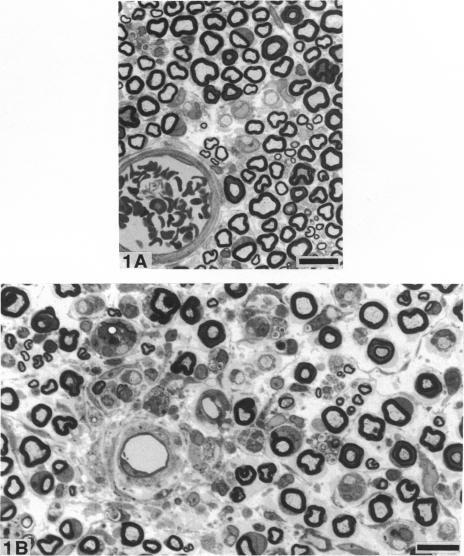

Nerve ischaemia plays a major role in the development of pathological alterations in various neuropathies, and the effects of ischaemia are amplified by reperfusion in various tissues. While pathological alterations in acutely ischaemic nerve have been established, nerve pathology resulting from reperfusion injury has never been elucidated. To evaluate what cell type in peripheral nerve is affected by reoxygenation following a hypoxic episode, we developed an animal model of transient severe limb ischaemia. Near-complete ischaemia, confirmed by the measurement of nerve blood flow, was achieved by clamping multiple arteries of supply to rat hindlimb. After 3, 5 or 7 h of limb ischaemia, vascular clips were released to reperfuse blood flow. Pathology in sciatic, tibial and peroneal nerves at the lower thigh level was examined at 7 d after reperfusion. All reperfused nerves developed demyelinated nerve fibres, particularly in perivascular regions. Although 3 h of ischaemia followed by reperfusion caused demyelination, perivascular demyelination was more prominent after a longer period of ischaemia with reperfusion. Two types of nerve oedema were observed; endoneurial oedema especially in perivascular and subperineurial spaces, and intramyelinic oedema. Nerve fibres with intramyelinic oedema were not confined to the perivascular region. Swollen endothelial cells in endoneurial vessels were also invariably observed. Nerve ischaemia per se, without reperfusion, did not induce these pathological changes. Because myelin appears to be particularly susceptible to activated free radicals, oxidative stress, activated neutrophils, and cytokine formation seem to be important underlying mechanisms in the development of perivascular demyelination and intramyelinic oedema in ischaemic/reperfused nerves.(ABSTRACT TRUNCATED AT 250 WORDS)

神经缺血在各种神经病变的病理改变发展过程中起主要作用,并且缺血的影响在各种组织中会因再灌注而放大。虽然急性缺血性神经的病理改变已得到确认,但再灌注损伤导致的神经病理变化从未被阐明。为了评估缺氧发作后外周神经中哪种细胞类型受复氧影响,我们建立了一个短暂性严重肢体缺血的动物模型。通过夹闭大鼠后肢的多条供血动脉实现了近乎完全的缺血,这通过测量神经血流得以证实。肢体缺血3、5或7小时后,松开血管夹以恢复血流。在再灌注7天后检查大腿下部水平的坐骨神经、胫神经和腓总神经的病理情况。所有再灌注的神经都出现了脱髓鞘神经纤维,特别是在血管周围区域。虽然缺血3小时后再灌注会导致脱髓鞘,但长时间缺血后再灌注时血管周围脱髓鞘更为明显。观察到两种类型的神经水肿:特别是在血管周围和神经束膜下间隙的神经内膜水肿,以及髓鞘内水肿。有髓鞘内水肿的神经纤维并不局限于血管周围区域。神经内膜血管中肿胀的内皮细胞也总是能被观察到。单纯的神经缺血,无再灌注,不会诱发这些病理变化。因为髓鞘似乎对活化的自由基特别敏感,氧化应激、活化的中性粒细胞和细胞因子形成似乎是缺血/再灌注神经中血管周围脱髓鞘和髓鞘内水肿发展的重要潜在机制。(摘要截短至250字)